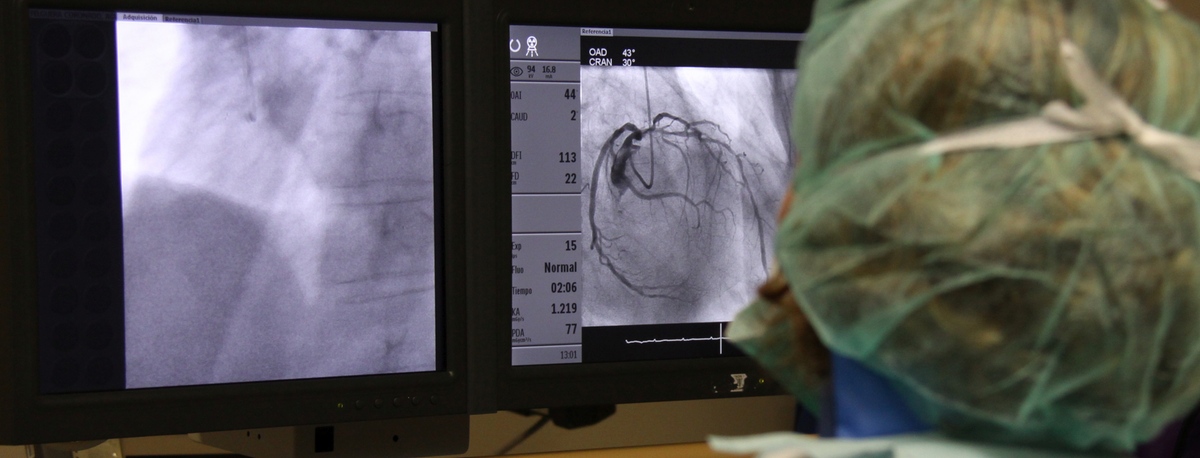

Instituto del Corazón

Instituto del Corazón Quirónsalud Teknon

En el instituto contamos con especialistas en Angiología, Cirugía Vascular y Endovascular para el diagnóstico y seguimiento de las enfermedades del aparato circulatorio. La embolia cerebral y el tromboembolismo pulmonar son algunas de las principales causas de muerte debido a un problema vascular.

Nuestro equipo es especialista en técnicas mínimamente invasivas, utilizando técnicas endovasculares, sin cirugía, que permiten implantar prótesis vasculares para resolver dilataciones o aneurismas de las arterias. También ofrecemos todos los tratamientos de la patología venosa y arterial periférica, incluyendo las enfermedades de las arterias carótidas.